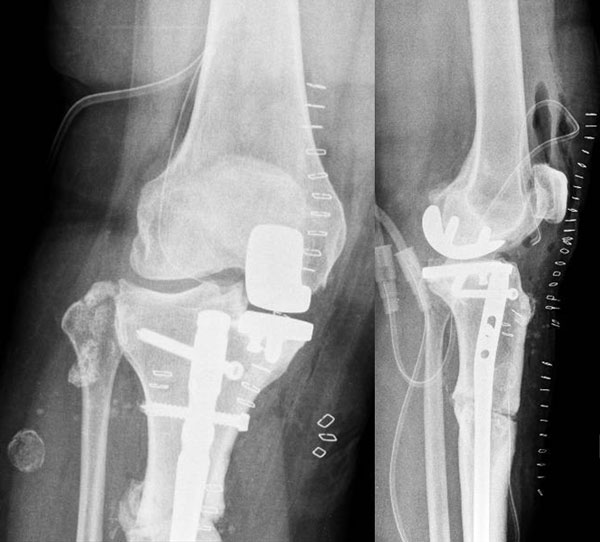

Management of a post-traumatic knee pain: Pre-op XRays

Pre-op XRays